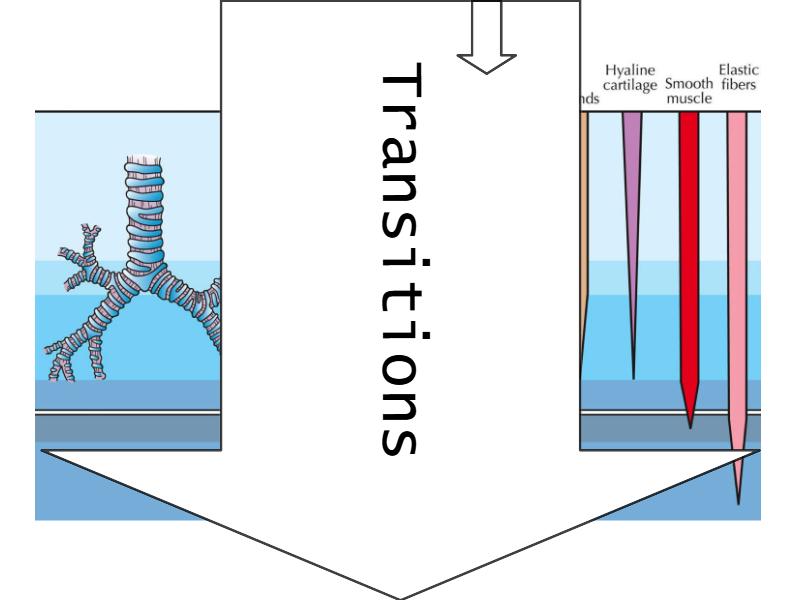

Transitions

Bronchi - Transitions

- Intrapulmonary bronchi

- Irregular cartilage

- Respiratory epithelium

- Glands

- Bronchioles

- Smooth muscle REPLACE cartilage

- Ciliated columnar > Ciliated cuboidal

- NO glands - goblet cells -> secretory cells

- Terminal bronchioles

- Smooth muscle

- Ciliated cuboidal epithelium

- Secretory cells

- Respiratory bronchioles

- Conducting -> Respiratory

- Simple cuboidal epithelium

- Secretory cells

- Alveoli